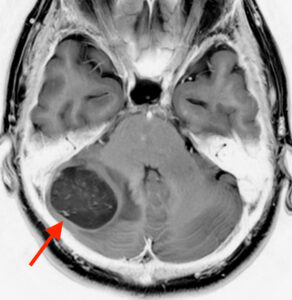

MRI検査をしたところ、

右の小脳に直径3.6mm位の脳腫瘍が見つかりました。小脳は体のバランスをコントロールしている場所で、ここが侵されるとめまいやふらつきを感じるようになります。